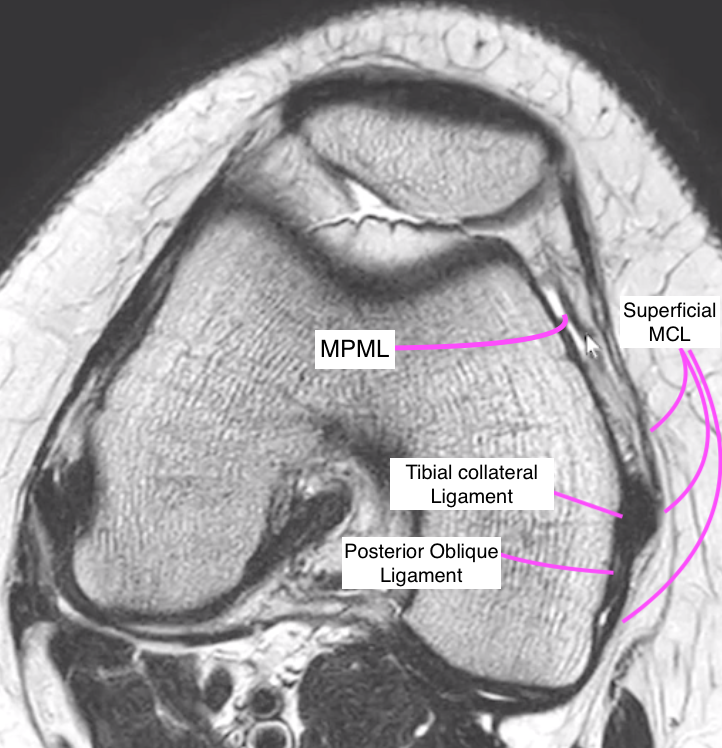

Posterior Medial corner

• Semimembranosus tendon (5 arms)

• Knee Capsule

Medial Knee Stabilizers

• Can be thought of in 2 ways, layers or thirds

• Layers

• Layer 1 = fascia

• Layer 2 = Superficial MCL

• Layer 3 = Deep MCL and capsule

• Issue here is that many of these will fuse

• Anteriorly layers 1 & 2 fuse to medial retinaculum

• Posteriorly 2 & 3 fuse to posterior oblique ligament

• Thirds

• Anterior third = Medial retinacular ligaments + Pes Anserinus

• Medial patellofemoral ligament

• Attaches from medial patella to the tibial collateral ligament (TCL) (medial collateral ligament)

• Fibers attach to the inferior aspect of the vastus medialis muscle

• Medial patellomeniscal ligament

• Extends from medial patella along an inferior-oblique path to the anterior horn of the medial meniscus

• Medial patellotibial ligament (MPTL)

• Extends from medial patella along an inferior-oblique path to the anterior surface of the medial tibial plateau

• Middle third

• Superficial & Deep MCL

• Medial capsular ligament

• Posterior third

• Posterior oblique ligament

• Oblique popliteal ligament

• Semimembranosis complex